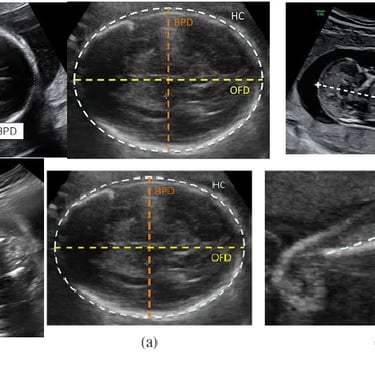

Fetal biometric measurements are important components for evaluation of fetal age on Ultrasound

Fetal biometry is a medical test used to assess the health and development of a fetus during pregnancy. This test uses ultrasound technology to measure the fetus's age, weight, and physical structure.

The technician will measure the fetus's age, weight, and physical structure